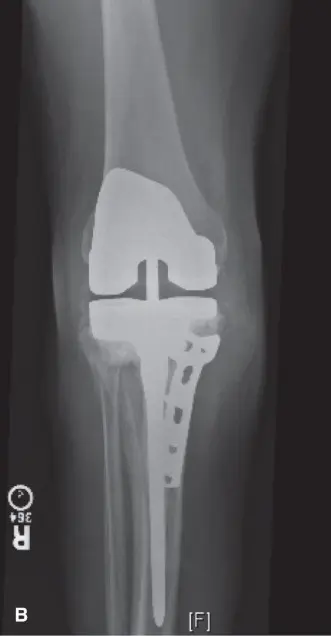

في حالة المريض الذي نناقشه، أظهرت الأشعة السينية علامات تآكل في البولي إيثيلين، تضييق في المسافة المفصلية الإنسية، وخطًا شفافًا حول المكون الظنبوبي يشير إلى تخلخل محتمل. كما كشفت عن محور ميكانيكي قوسي (varus) بمقدار 8 درجات.

(الشكل 1. صورة بالأشعة السينية الأمامية الخلفية توضح تخلخلًا محتملًا في مكون الظنبوب، تآكلًا في البولي إيثيلين، وسوء محاذاة قوسي.)